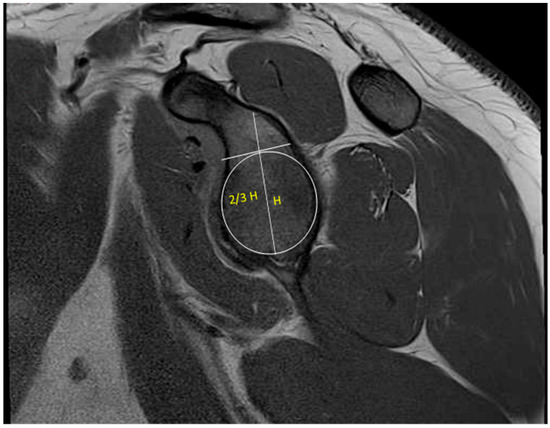

The radiologic evaluation of shoulder instability should begin with plain radiographs. The standard initial set includes an anteroposterior (AP) view in the plane of the scapula (i.e., a “true” AP or Grashey view), a scapular “Y” lateral view, and an axillary view. Orthogonal imaging is crucial in assessing whether the humeral head is concentrically reduced and can be helpful in determining direction of instability.

Additional imaging can include the Stryker notch, West Point, and Bernageau views (Figure 4). The Stryker notch view is obtained with the patient supine and the cassette under the affected shoulder. The patient’s ipsilateral hand is placed on top of the head with their fingers towards the occiput. The X-ray is shot with the beam tilted ten degrees cephalad and centered over the coracoid process [22]. The Stryker notch view can help identify Hill–Sachs lesions with a reported sensitivity of 81% and specificity of 100% [23,24]. The West Point view allows for a tangential view of the anteroinferior glenoid rim. The view is obtained with the patient prone and the affected shoulder raised with a bump approximately 8 cm above the table with the forearm dangling free. The cassette is held against the superior aspect of the shoulder, and the beam is aimed at the axilla at a 25-degree angle downward and medially [22]. The Bernageau view is obtained with the patient standing with the arm at maximal forward flexion, usually 160 degrees. The cassette is placed in contact with the thorax at an angle of 70 degrees, and the X-ray is shot 30 degrees caudally and centered on the scapular spine [25]. Edwards et al. found that 79% of osseous abnormalities of the glenoid may be identified utilizing the Bernageau view [26]. Murachovsky et al. described a method of using the Bernageau view to calculate glenoid bone loss. The anterior-to-posterior distance of the glenoid was measured and then compared to the contralateral side to determine the percentage of bone loss. This method was reproducible with an interobserver correlation coefficient of 0.81 and demonstrated comparable results to 3D CT [25].

Figure 4. (A) Stryker notch, (B) West Point, and (C) Bernageau views.

Jcm 13 07708 g004